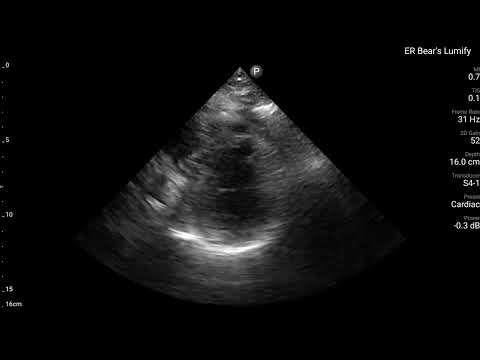

當下有幫病患做echo,讓我們來看看echo有哪些findings?

藉由echo,我們可以看到,LAD支配的Ant.wall幾乎不太動。(請搭配Fig.4安心服用)

ECG在LAD支配位置的Precordial leads出現Subtle STE/PRWP/HATW/此外10分鐘後的dynamic STTC,另外加上echo看到ant.wall有RWMA。這些證據不管怎麼樣都實實在在說明,LAD出現問題了。